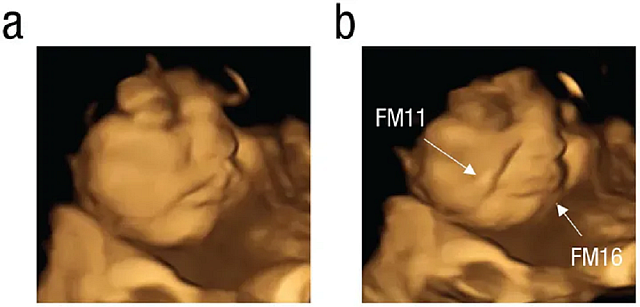

Το τράβηγμα της γωνίας των χειλιών, που υποδηλώνει χαμόγελο ή γέλιο, ήταν σημαντικά υψηλότερο στην ομάδα του καρότου σε σύγκριση με την ομάδα της λαχανίδας και την ομάδα ελέγχου. Ενώ κινήσεις όπως η ανύψωση του άνω χείλους, η ρίψη του κάτω χείλους προς τα κάτω, το πάτημα των χειλιών και ένας συνδυασμός αυτών - που υποδηλώνει ένα πρόσωπο που κλαίει - ήταν πολύ πιο συχνές στην ομάδα της λαχανίδας σε σχέση με τις άλλες ομάδες.

Οι εξελίξεις στην τεχνολογία έχουν επιτρέψει καλύτερες εικόνες των προσώπων των εμβρύων στη μήτρα, σύμφωνα με την καθηγήτρια Nadja Reissland, επικεφαλής του Εργαστηρίου Εμβρυϊκής και Νεογνικής Έρευνας στο Πανεπιστήμιο Durham. Η Reissland, η οποία επέβλεψε την έρευνα, ανέπτυξε το σύστημα Fetal Observable Movement System (FMOS), με το οποίο κωδικοποιήθηκαν οι 4D λήψεις.

«Καθώς η τεχνολογία εξελίσσεται, η απεικόνιση με υπερήχους γίνεται καλύτερη και ακριβέστερη», δήλωσε στο CNN, προσθέτοντας ότι αυτό «μας επιτρέπει να κωδικοποιούμε τις κινήσεις του προσώπου του εμβρύου καρέ-καρέ με λεπτομέρεια και με την πάροδο του χρόνου».